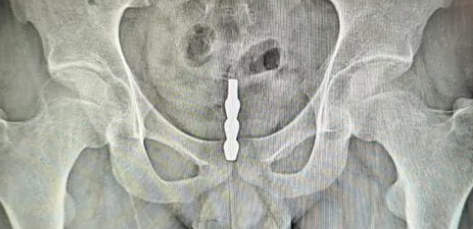

接诊的泌尿外科林主任通过膀胱镜观察到,金属异物表面的螺旋纹路已造成多处黏膜损伤。在精密微创手术中,医生们用了40分钟才将这件特殊"纪念品"完整取出。术后CT片显示,钢管距离穿透膀胱壁仅差2毫米。